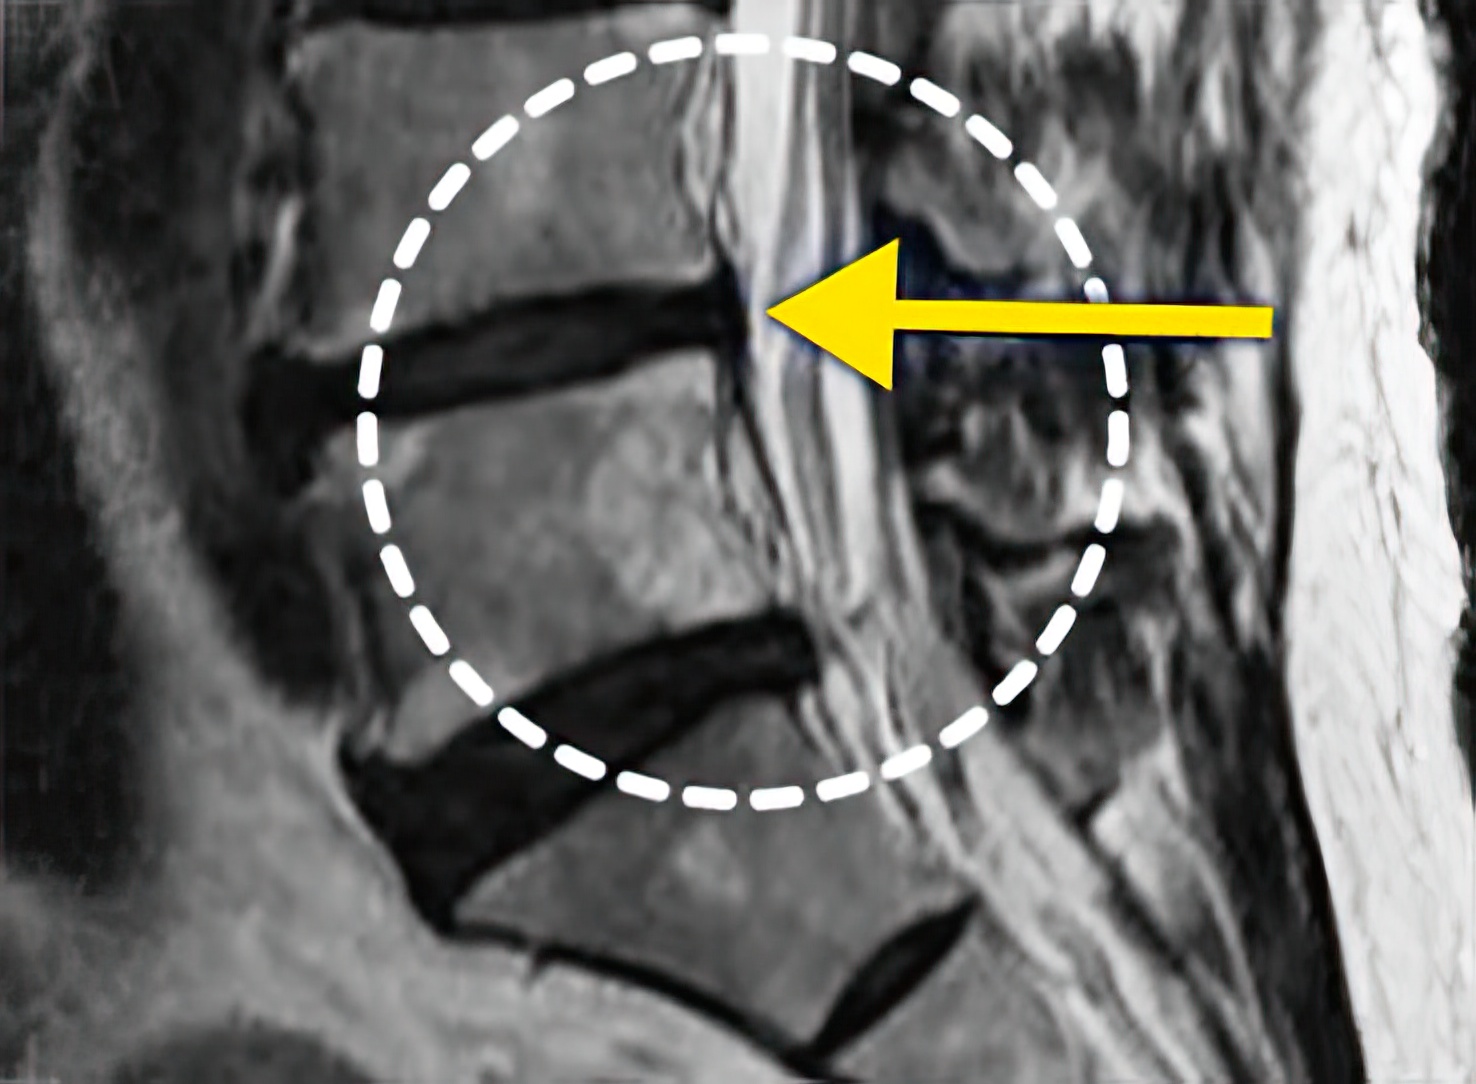

자생 비수술 한방통합치료 후

터진디스크가 흡수된 모습

Before

터진디스크 한방통합치료 전

After

터진디스크 한방통합치료 후

비수술 치료만으로

터진 디스크 흡수